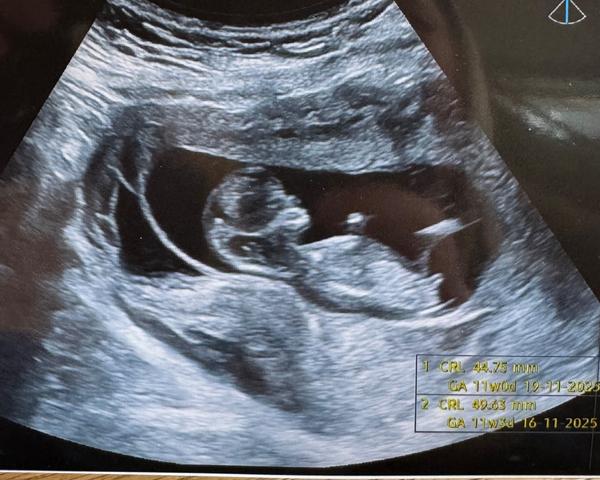

Pohlaví miminka z ultrazvuku. Lze rozpoznat?

Ahoj mam dotaz 😁 věděl by někdo jestli holčička nebo chlapeček? 😁

My byli včera na screeningu, úplně stejný obrázek nám dala doktorka a i přes toho malého 'pinďu' nám řekla, že je to na 85% holčička 😃

@bebyna No on ten hrbolek tam totiž neni pinďour, ale pohlavni hrbolek. Ma to jak chlapecek tak i holcicka. Samotne pohlavi videt v techto tydnech neni. Porovnava se poloha pohlavniho hrbolku s pateri.

Je to jeste dost brzy, ale podle nub teorie bych rekla holcicka.